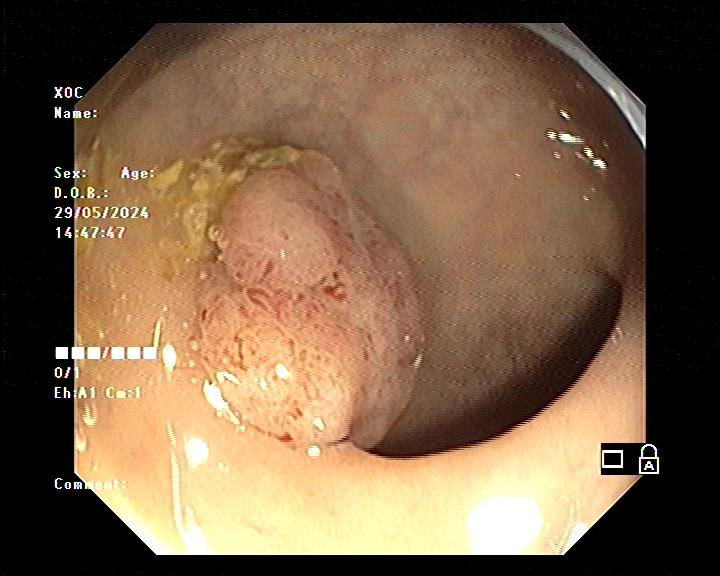

Làm gì khi phát hiện có polyp trong đại tràng? Khi phát hiện polyp đại tràng, bác sĩ có thể cắt bỏ nó và làm xét nghiệm tìm xem có tế bào ung thư hay không. Hầu hết các polyp được loại bỏ trong quá trình nội soi đại tràng.